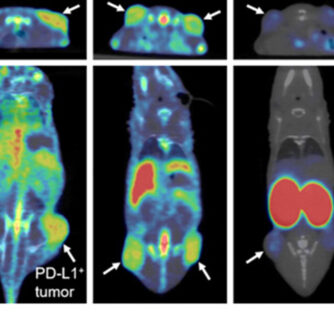

Marqueur prédictif pour immunothérapie